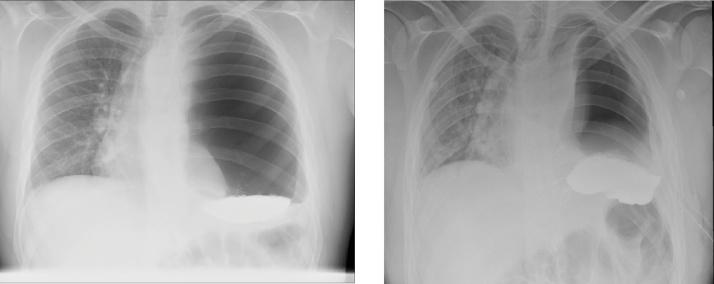

We report the case of a 20-year-old male who presented to the emergency department with progressively worsening upper abdominal pain, nausea and vomiting followed by acute onset dyspnoea, six days post a laparoscopic repair of a small hiatus hernia and a Nissen fundoplication. His chest x-ray was consistent with that of a left sided pneumothorax and was therefore, appropriately resuscitated and treated with an intercostal catheter (ICC). A subsequent CT scan of the chest revealed a left gastrothorax. The patient was taken to theatre for the surgical reduction of the paraoesophageal hernia.

我们报告一例20岁男性病例,该患者在腹腔镜修复小型食管裂孔疝和进行nissen胃底折叠术后6天,因上腹部疼痛、恶心和呕吐逐渐加重,随后急性发作呼吸困难而就诊于急诊科。他的胸部X光片与左侧气胸相符,因此进行了适当的复苏,并采用肋间导管(ICC)进行治疗。随后的胸部CT扫描显示为左膈下胃疝。患者被送往手术室进行食管旁疝的手术复位。